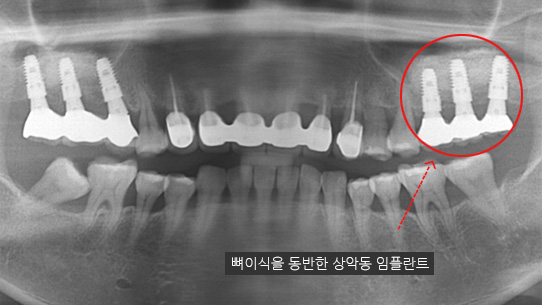

타 치과 에서 6개 치아를 발치하고 12개 임플란트 식립을 진단받고 내원. 고운미소에서 치주치료를 통하여

치아를 보존 시키고 6개의 임플란트 식립한케이스

잇몸뼈가 녹아내려 다른 병원에서 임플란트 12개 진단을 받고 내원, 고운미소에서 치주치료를 시행한 결과 전치부 잇몸이 개선되어 발치 하지 않고

크라운으로 수복하였고, 어금니에 6개의 임플란트를 식립하였습니다.